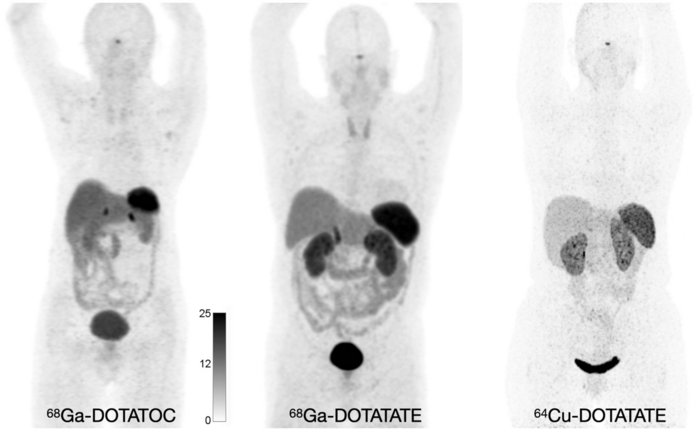

Normal biodistribution of 68Ga-DOTATOC, 68Ga-DOTATATE, and 64Cu-DOTATATE.

Hope TA, Allen-Auerbach M, Bodei L, Calais J, et al., SNMMI Procedure Standard/EANM Practice Guideline for SSTR PET: Imaging Neuroendocrine Tumors. J Nucl Med. 2023 Feb;64(2):204-210.